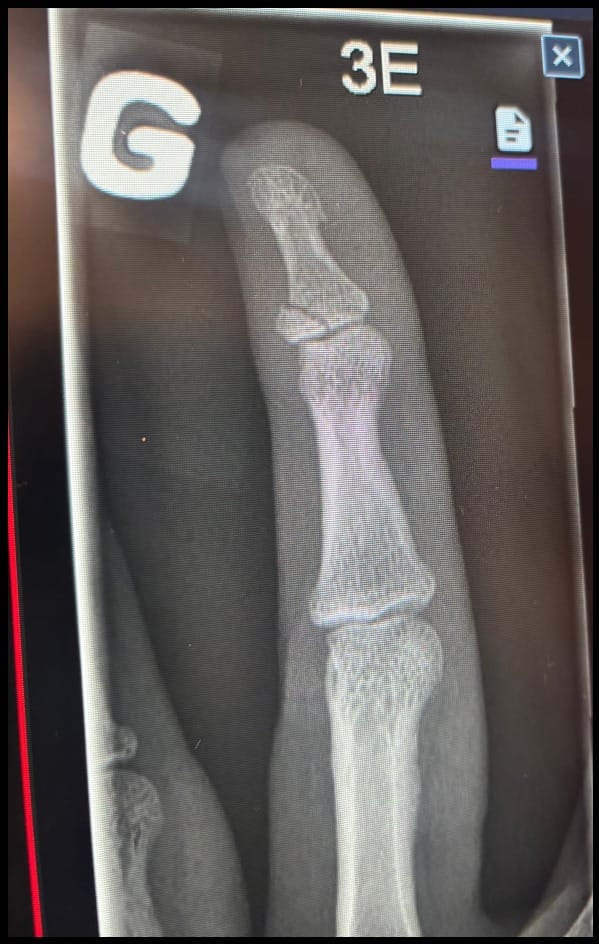

Embarrassed to tell people what caused the damage, I was proud to share that it wasn’t the result of a bike accident. Though we’re made of things that break and bend, I was too stubborn to get help for the awkward-looking finger until everyone, including my dentist, threw just the right amount of shame my way. My period of denial ended when I saw the X-ray, and I emerged shortly after the scan from the hospital with what looked like a plastic toboggan taped to my break. Luckily, people around me pushed for a repair and found the parts I needed to move on, one for my finger and one for my bike. The next stage of my grief was anger.